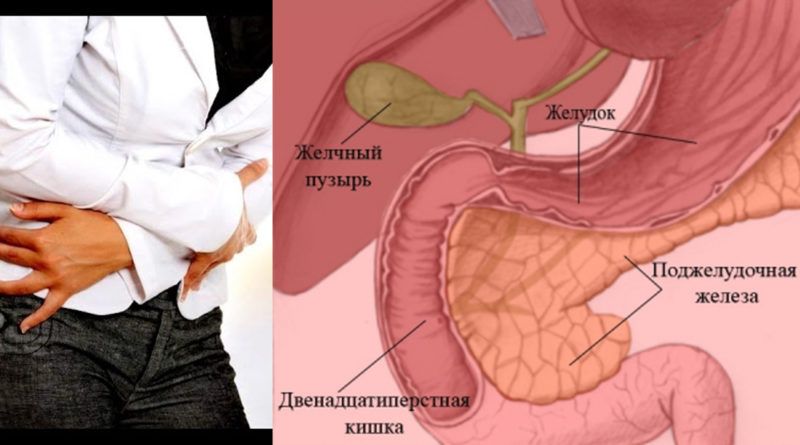

Оттого, где находится поджелудочная железа, зависит и как она болит. Боли, возникающие при нарушении функций ПЖ, носят разный характер. Это могут быть тянущие тупые, или режущие острые. Боли кинжального типа говорят о том, что заболевание запущено и возможно начало перитонита, когда в воспаление вовлечены оболочки брюшины.

Панкреатит острой формы, сопровождающийся отеками прилегающих к ПЖ тканей, дает резкую внезапную боль опоясывающего типа. Она распространяется вверх живота, в левое подреберье, в поясницу.

Отечность добавляет распирающее ощущение на месте ПЖ, поддавливание изнутри ребер.

При таких состояниях спазмолитики и другие обезболивающие неэффективные. Боль несколько стихает, если человек садится и наклоняется вперед, вниз. При отсутствии болей или на их пике может случиться рвота, неоднократная и не приносящая болевого облегчения.

Когда воспаление начинается в одной из частей ПЖ, то это выражается особыми симптомами:

- воспаленная головка дает боли под правыми ребрами;

- воспаление в теле шлет сигнал боли в подложечную зону;

- воспаление, затрагивающее хвост органа, отдает болями под левые ребра;

- воспаление, охватывающее весь орган, дает боли опоясывающего типа, простреливает спину, основные боли локализуются под левой лопаткой.

Где находится часть железы, там и проявляются основные боли. Однако при общем воспалении боль стреляет в пах, копчик, начинают болеть бедра, промежность. Такое разнообразие болей существенно затрудняет диагностику.

Боли в животе при нарушении пищеварения возникают от разных патологий. Врачу важно провести дифференциальную диагностику, выяснить причины, чтобы начать направленное лечение болезни.